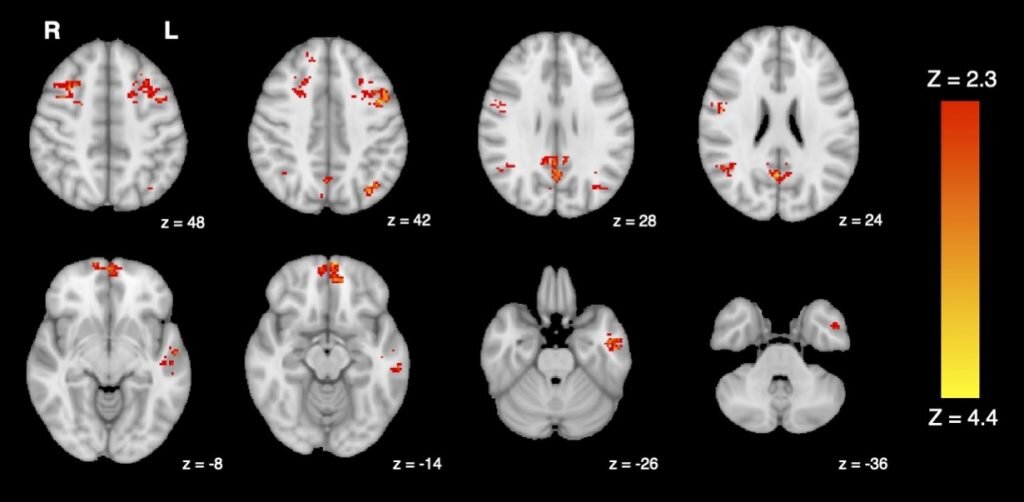

Исследование показало уменьшение функциональной связности — характеристика, которая говорит о том, насколько хорошо различные области мозга коммуницируют друг с другом — в обширных регионах СПРРМ после воздействия выхлопных газов дизельного двигателя.

Снижение функциональной связности СПРРМ на фМРТ. Изображение: Jodie R. Gawryluk et al., Environmental Health, University of British Columbia